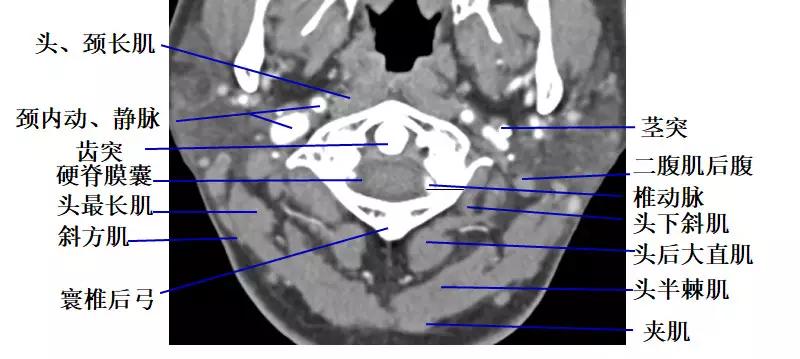

2.经环枢关节的横断层面(CT)